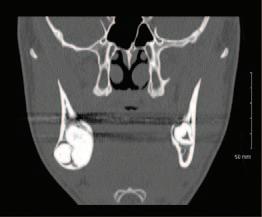

7. Dewey, K.W. Osteoma of a molar. Dent Cosmos 1927; 69: 1143-1149.

8. Pindborg, J.J., Kramer, I.R. Histological Typing of Odontogenic Tumor, Jaw Cysts and Allied Lesions. World Health Organisation, Geneva 1971: 31.

9. El-Naggar, A.K., Chan, J.K.C., Grandis, J.R., Takata, T., Slootweg, P.J. (eds.). WHO Classification of Head and Neck Tumours. WHO/IARC Classification of Tumours (4th Ed.). 2017, Volume 9.

CPD questions